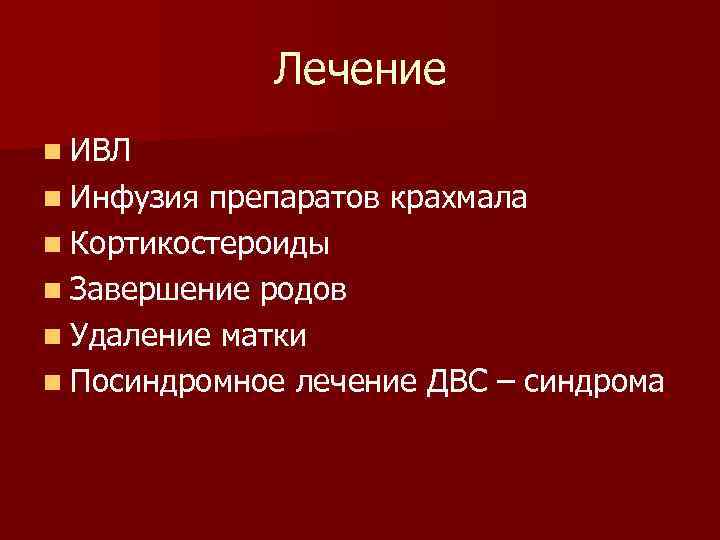

Лечение n ИВЛ n Инфузия препаратов крахмала n Кортикостероиды n Завершение родов n Удаление матки n Посиндромное лечение ДВС – синдрома

Лечение n ИВЛ n Инфузия препаратов крахмала n Кортикостероиды n Завершение родов n Удаление матки n Посиндромное лечение ДВС – синдрома